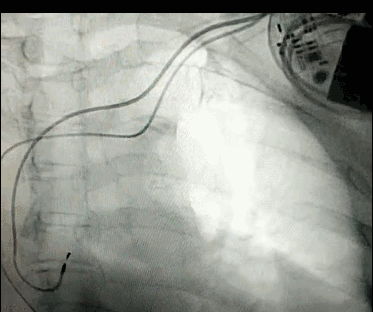

腦血管成像的“金標(biāo)準(zhǔn)”!——DSA三部曲之技術(shù)篇

DSA是將造影劑注入需要檢查的血管中,使血管顯露原形,然后通過(guò)系統(tǒng)處理,使血管顯示更加清晰,便于醫(yī)生診斷或進(jìn)行手術(shù)。

淺析DSA的前世今生!

數(shù)字減影血管造影術(shù)是醫(yī)學(xué)影象學(xué)中,繼X線(xiàn)CT之后的又一項(xiàng)新技術(shù),也是當(dāng)前醫(yī)學(xué)影象學(xué)中具有突破性的重大進(jìn)展。?